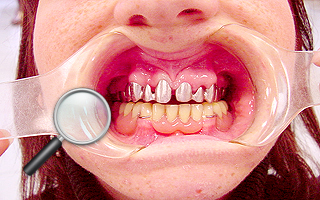

5. Pacjentka lat 18 z wrodzonym brakiem wielu zębów tzw. hipodoncją – rehabilitacja protetyczna z wykorzystaniem

stałych mostów porcelanowych na podbudowie metalowej.

| 5a. Stan przed leczeniem |

5b. RTG panoramiczne |

| 5c. Uzupełnienia tymczasowe na okres leczenia |

5d. Próba struktury metalowej mostu porcelanowego górnego |

| 5e. Gotowy most porcelanowy górny i próba struktury metalowej dolnej |

5f. Gotowe mosty porcelanowe |